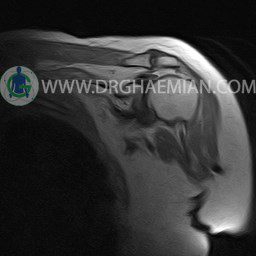

ام آر آی آتروفی عضلانی کتف بیمار

ام ار آی کتف یک روش تصویربرداری است که به وسیله آهنرباهای قدرتمند از قسمت کتف تصاویری ایجاد می کند. این نوع تصویربرداری از تشعشعات استفاده نمی کند. در این کیس آتروفی عضلانی کتف به همراه پارگی تاندون بالاخاری، بورسیت ساب دلتوئید و افیوژن مفصل دیده می شود.

– Complete tearing of supraspinatus tendon with grade 2 retraction and muscle atrophy

– AC joint hypertrophy with subacromial – subdeltoid bursitis

– Glenohumeral joint effusion

are seen.